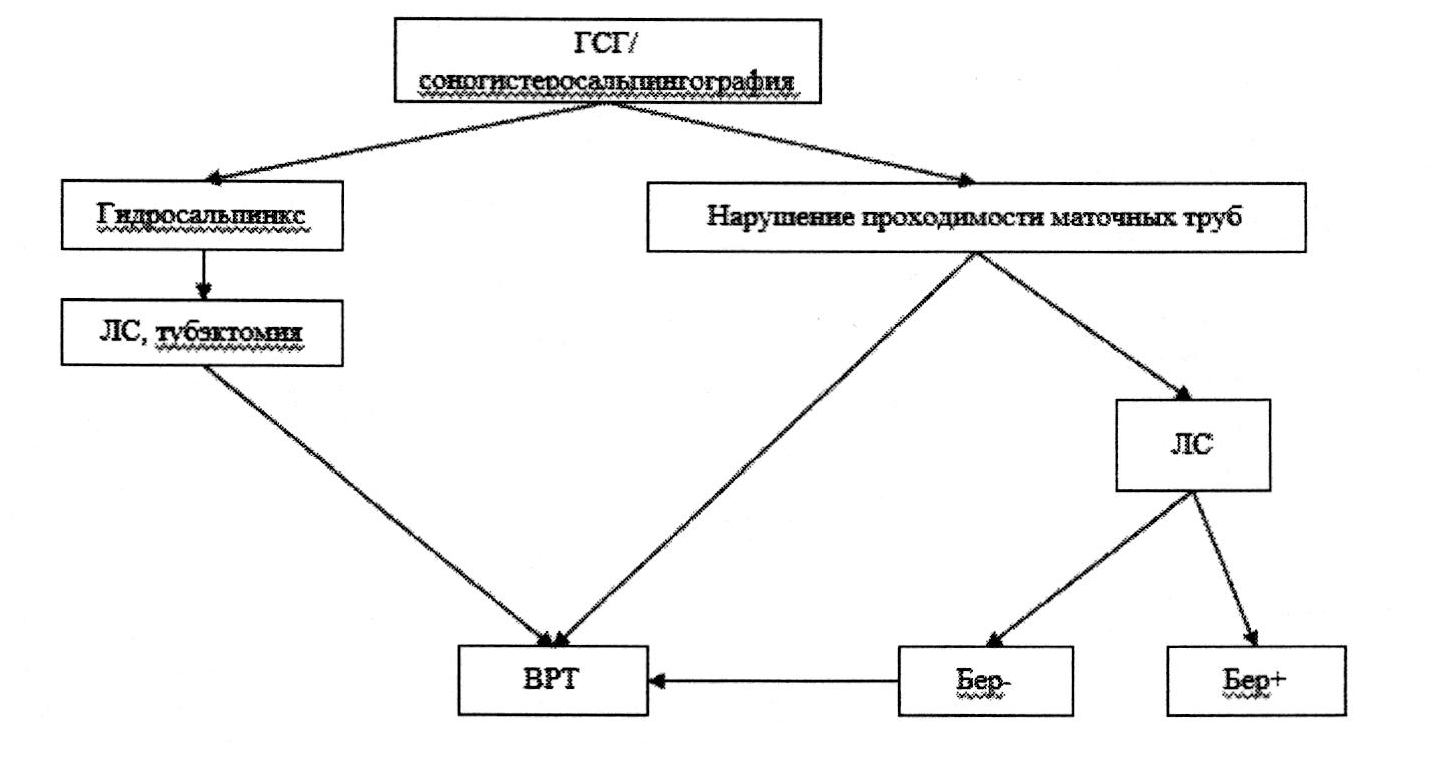

5. Женское бесплодие трубного происхождения (MKБ-10/N97.1)

Определение. Трубное бесплодие обусловлено нарушением проходимости маточных труб вследствие аномалии развития, в результате перенесенного воспаления (сальпингита) или отсутствия маточных труб. В воспалительный процесс могут вовлекаться яичник (сальпигооофорит, аднексит) и брюшина малого таза. Бесплодие, связанное с сочетанием непроходимости маточных труб и спаечным процессом, в отечественной практике получило название «трубно-перитонеальное».

Этиологические факторы:

Эпидемиология. Частота трубно-перитонеального бесплодия в России - 25-70% [50].

Диагностика

Рекомендовано проведение ГСГ или соногистеросальпингография для оценки состояния маточных труб.

Возможные результаты при ГСГ:

- непроходимость маточных труб в интерстициальном или истмическом отделах (визуализация маточных труб до истмического отдела);

- непроходимость маточных труб в ампулярном отделе (визуализация маточных труб на всем протяжении, отсутствие излития контрастного вещества в брюшную полость);

- увеличение размеров маточных труб (сактосальпинксы);

- неравномерное распределение контрастного вещества в малом тазу, подтянутость труб к костям таза, излитое контраста в небольшом количестве (затрудненная проходимость труб).

Лечение

- Консервативное лечение, направленное на достижение беременности при трубно-перитонеальном бесплодии, неэффективно.

- Метод достижения беременности 1-й линии - применение ВРТ.

- Лапароскопия проводится при наличии показаний [51].

Уровень доказательности С.

Виды реконструктивно-пластических операций при трубно-перитонеальном бесплодии с использованием эндовидеохирургии:

- сальпинголизис (освобождение маточных труб от деформирующих их спаечных сращений);

- фимбриопластика (восстановление входа в воронку маточной трубы);

- сальпингостомия (создание нового отверстия в заращенном ампулярном отделе);

- тубэктомия при наличии гидросальпинксов перед применением ВРТ.

Критерии отбора для хирургического лечения [51]:

- возраст до 35 лет;

- сохраненный овариальный резерв;

- подтвержденная овуляция;

- отсутствие патозооспермии у партнера.

Комментарии:

при наличии гидросальпинксов рекомендуется удаление измененных маточных труб;

повторные реконструктивно-пластические операции на маточных трубах для восстановления их проходимости и достижения беременности не показаны ввиду их неэффективности.